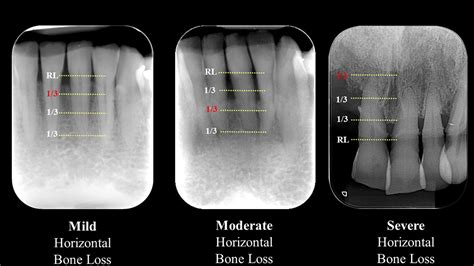

Formerly known as chronic periodontitis, this is the most common form. It occurs over a long period, characterized by the formation of deep pockets and/or gingival recession. It is most prevalent in adults but can occur at any age. Its progression is usually slow, but episodic bursts of rapid destruction can occur.

💡 Note: A professional dental examination including periodontal probing and X-rays is the only way to accurately confirm the severity and specific type of periodontal disease affecting your oral health.